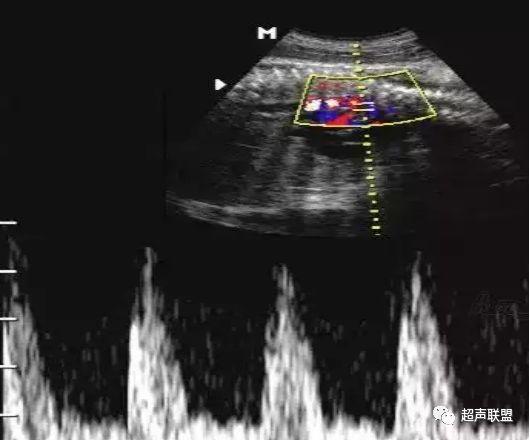

图9 脐静脉搏动